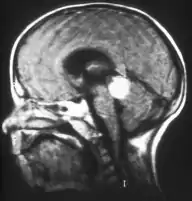

Aspect of trilateral retinoblastoma on MRI